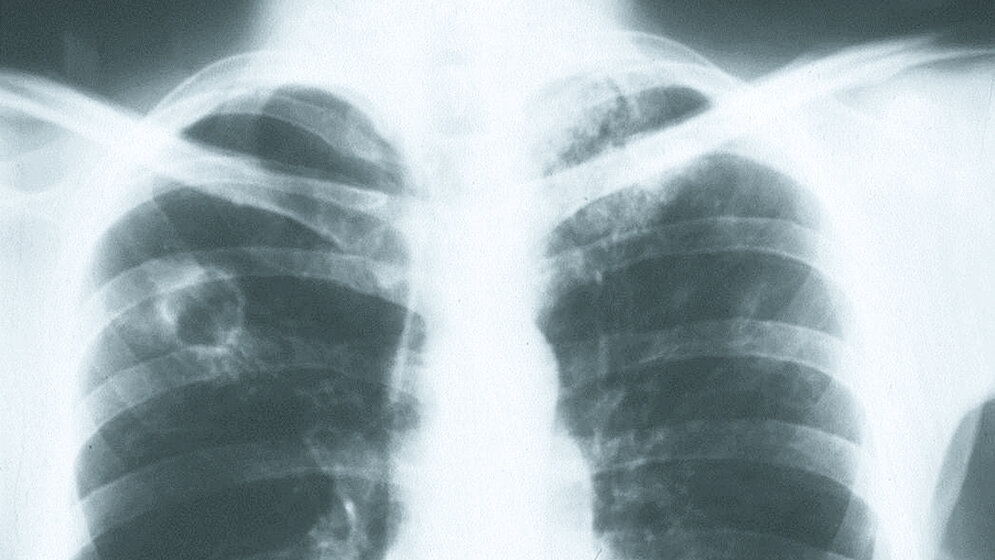

In outpatient clinics and hospitals, the occurence of unexpected cases of active tuberculosis (TB) often causes irritation among medical personal and contact patients. Occupational precautions such as wearing masks and gowns serves to lower the infection risk. In case of unprotected contacts with infectious patients, structured follow-up examinations by the occupational medical service are required. In case latent infection has occurred, preventive therapy reduces the risk of clinically overt infection.